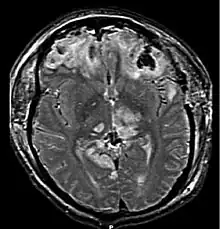

![]() TAC que muestra contusiones cerebrales, hemorragia entre los hemisferios, hematoma subdural en la izquierda y fracturas del cráneo. | ||

Hemorragias petequiales múltiples

Las numerosas contusiones producidas en los capilares rotos en la materia gris bajo la corteza se denominan múltiples hemorragias petequiales o contusión hemorrágica multifocal. Son causadas por lesiones de corte en el momento del impacto, las contusiones se producen sobre todo en la unión entre la materia gris y la materia blanca y en la parte superior del tronco cerebral, ganglios basales, el tálamo y las áreas cercanas al tercer ventrículo. Las hemorragias pueden ocurrir como resultado de una hernia cerebral, que puede causar que las arterias se rompan y sangren.[12] Un tipo de lesión cerebral difusa con múltiples hemorragias petequiales no siempre son visibles mediante las técnicas actuales como la Tomografía Axial Computerizada (TAC) y la imagen por Resonancia Magnética Nuclear (RMN). Se puede dar el caso, incluso si la lesión es muy grave, de presentarse días después de la lesión. Si la lesión es muy grave las hemorragias pueden ser más grandes que en las contusiones normales. Este tipo de lesión tiene mal pronóstico si el paciente está en estado de coma o comatoso.[13]